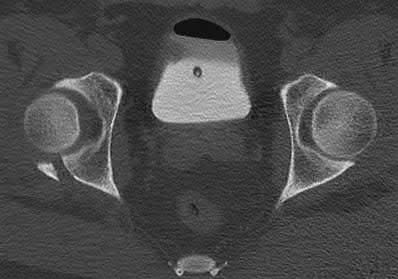

A 35 year-old female presents after prolonged extrication from a motor vehicle collision complaining of severe pelvic pain. Physical examination reveals diminished perianal sensation. She is otherwise neurologically intact. Figures A through D are radiographs and representative CT cuts of her injury. Which of the following nerve roots has likely been injured by the acute trauma?

The clinical scenario is consistent with a high-energy sacral fracture. The radiographs in figures A and B demonstrate a sacral fracture with posterior displacement of the right hemipelvis seen on the inlet view. Figures C and D are axial and sagittal CT images which show a displaced fracture of the right

hemisacrum along with a transvere fracture component through the S3 body . Diminished perianal sensation is concerning for an S2 nerve root injury.

Mehta et al reviewed the current management of sacral fractures. They note that the S1 and S2 nerve roots are more likely to be injured with sacral fractures as they occupy 1/3 to 1/4 of the neural foramina, as opposed to S3 and S4, which only occupy 1/6 of the neural foramina.

Robles reviewed the current literature to ascertain principles of evaluation and treatment for transverse sacral fractures. The author notes that injury to nerve roots S2 to S5 is manifested by impairment of urinary and anal continence and sexual function.